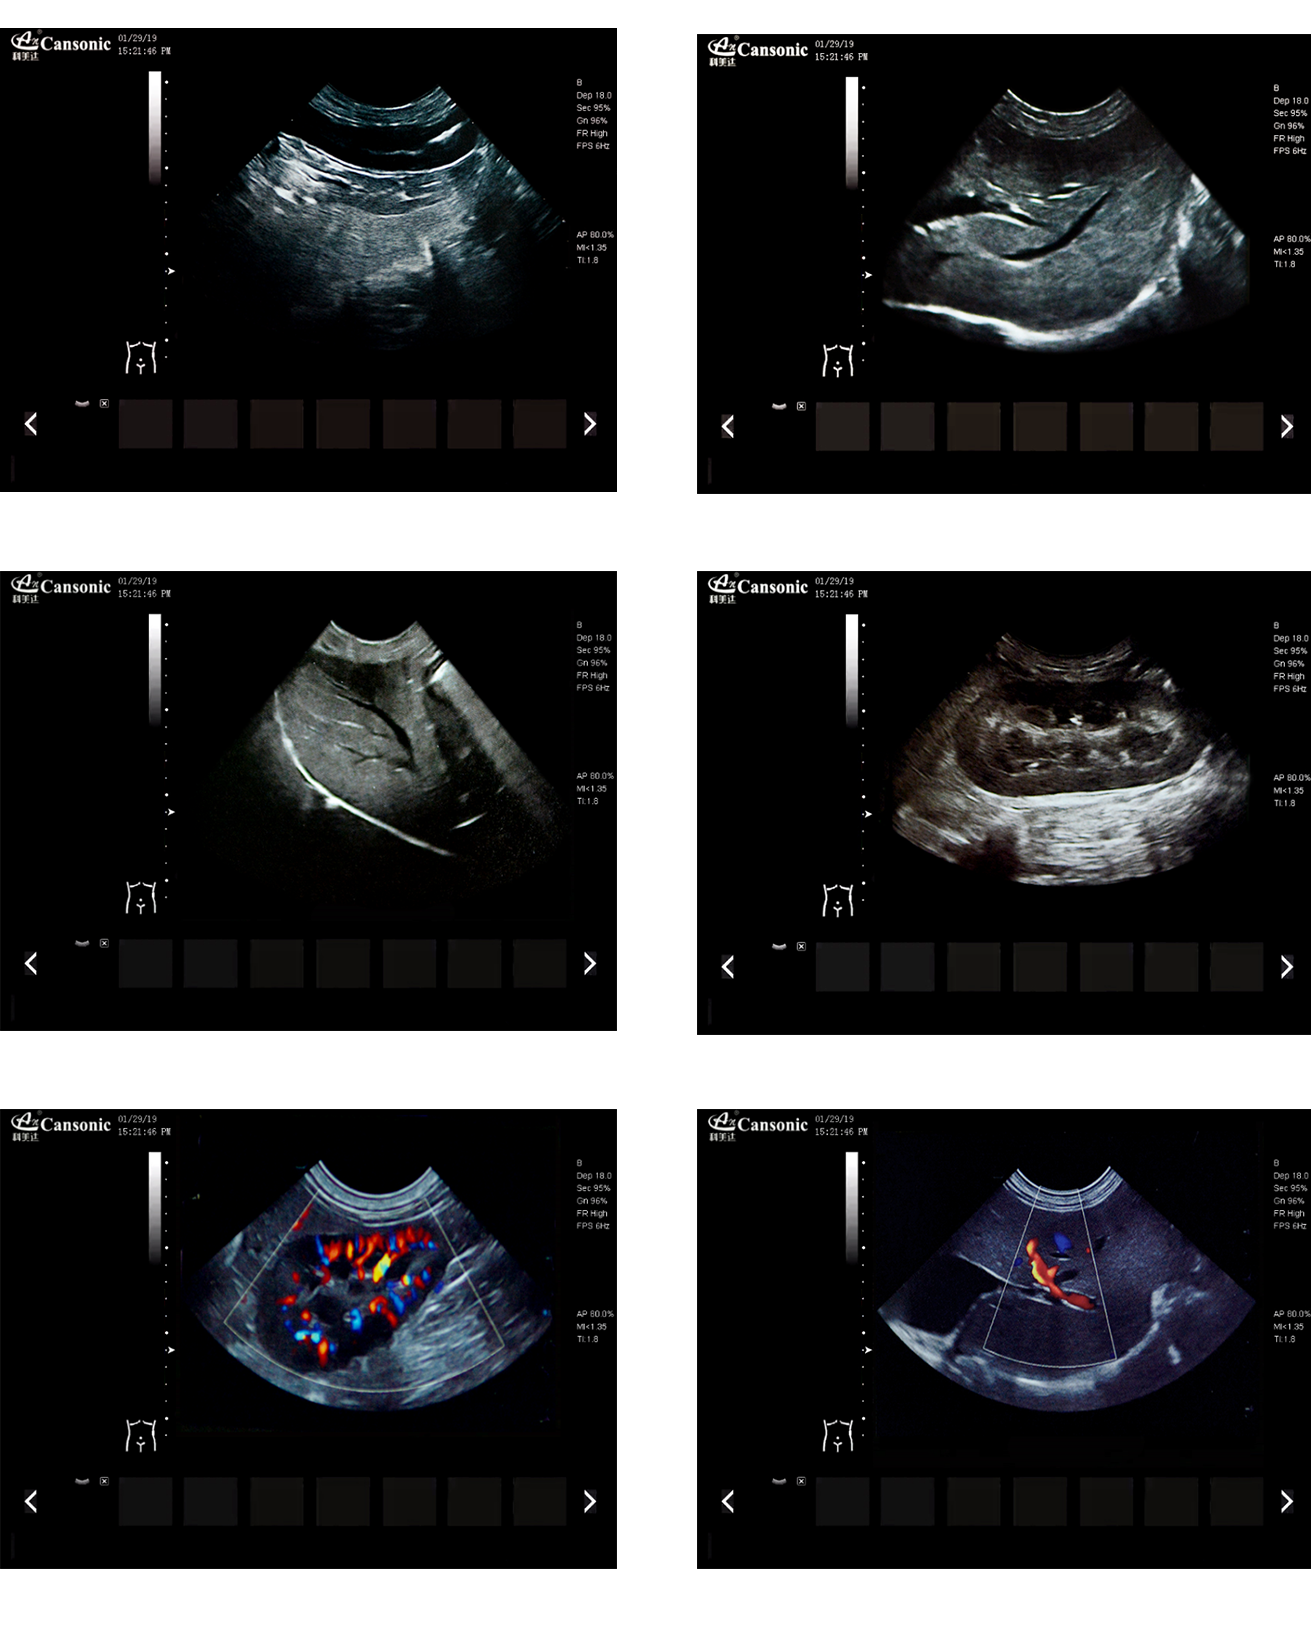

K2V

產(chǎn)品特點:

1、薈萃前沿成像技術(shù),實現(xiàn)高精與靈便的完美融合,提供完整的動物彩超診療方案

2、專業(yè)的獸用測量軟件,簡捷的工作流,適合犬、貓、馬、牛、羊等 各類大小動物

3、iClear斑點噪聲抑制抑制噪聲干擾,使動物組織結(jié)構(gòu)更清晰

4、具有廣泛的動態(tài)范圍,顯示出色的組織均勻性,減少了偽影及噪聲

5、精細血流識別技術(shù),增加了可疑病變更多的信息分析

6、先進的算法帶來清晰的穿刺針顯示,降低穿刺活檢操作難度

7、圖像優(yōu)異,同時性能穩(wěn)定,每天能進行大量的動物超聲檢查

8、輕巧的機身,耐摩損的把手,適應(yīng)各種復(fù)雜的動物使用環(huán)境

臨床圖示